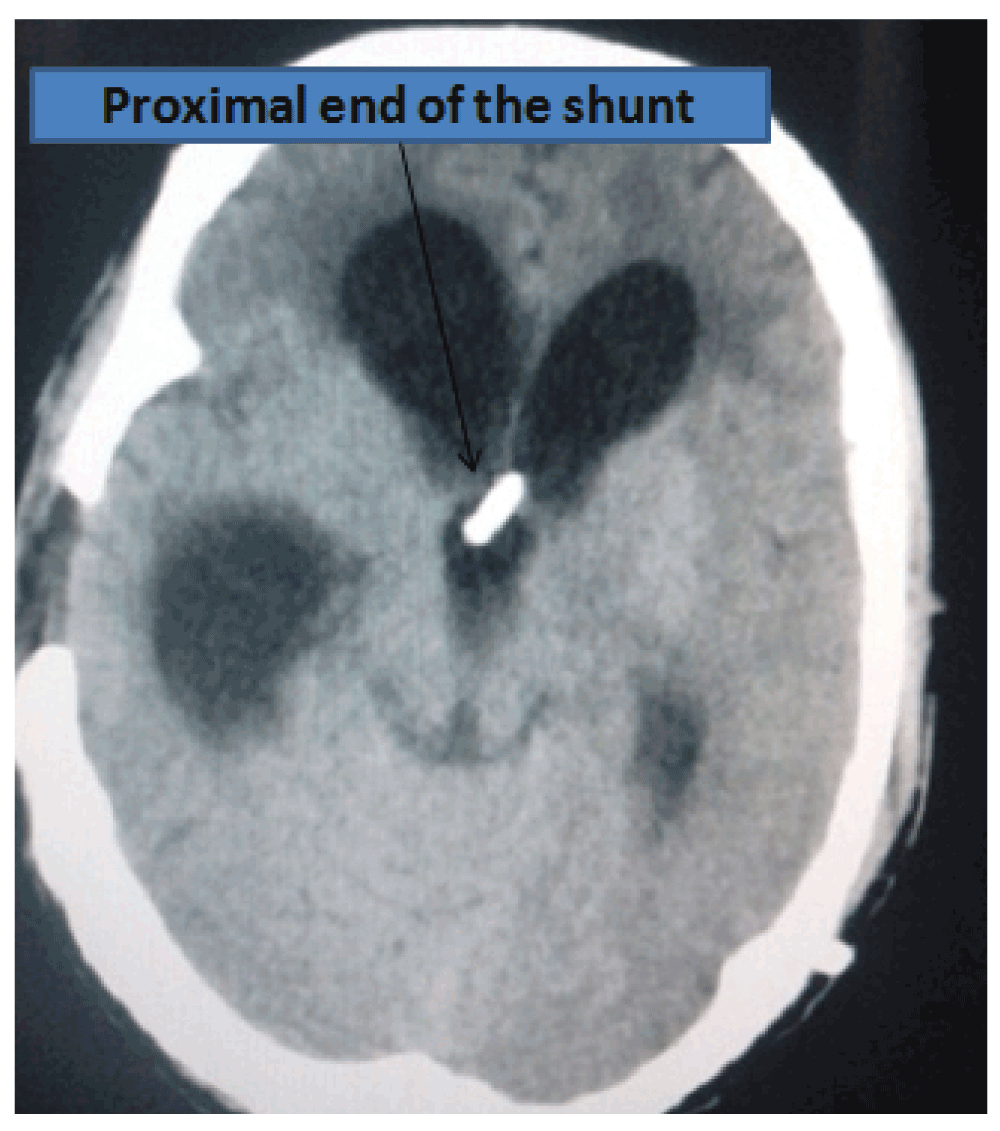

A postoperative scan revealed the presence of tension pneumocephalus and pneumoventriculi (Figure 1 and Figure 2). The patient was managed with 100% oxygen for 3 days and was continued on antiepileptic medications at the same dose intravenously. Stringent neurological monitoring was undertaken to evaluate early neurological deterioration due to tension pneumocephalus. Pupils were routinely assessed to look for hippus (a clinical marker of epilepsy). Patient was extubated the following morning. A repeat CT scan on the 6th day post-operation showed that the proximal shunt was in the third ventricle (Figure 3) and there was complete resolution of the condition. The EVD was subsequently removed with no neurological deterioration of the patient on 7th day after operation. The patient then started to walk with support from the 8th day post-operation, and he slowly improved in gait. Patient went home walking with minimal support on the 14th day post-operation. Patient had also regained his bladder control within that time. Patient returned, walking on his own 1 month later for his follow up in the outpatient department His gait was normal with no features of retropulsion. The shunt chamber was functioning well and his bowel habits were normal. Compliance in continuation of Sodium valproate therapy (at the aforementioned dose) was also ensured.

Figure 2. CT image showing location of EVD and VP Shunt proximal end.

Figure 3. CT image confirming location of proximal end of VP shunt.